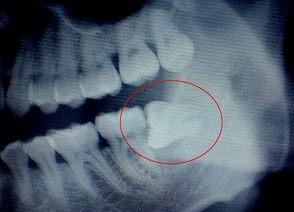

拔智齿,能瘦脸?智齿:想多了!